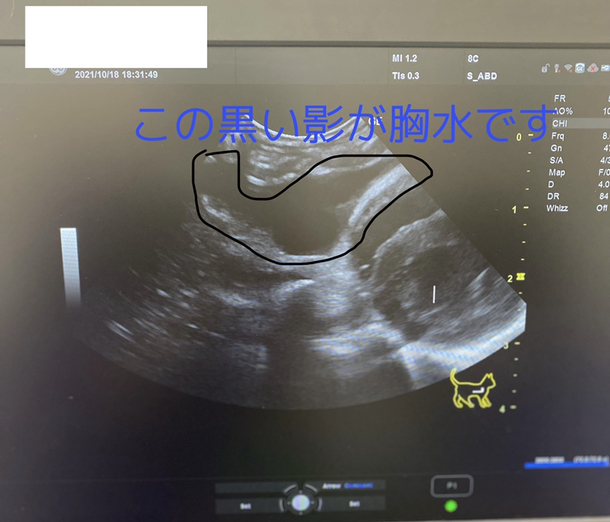

きなこもちの胸水

きなこもちの胸水は10/11,10/18共に右側に胸水が確認できていたのが、今回の診察では右側の胸水がほとんど貯まっていませんでした😭😭😭

画像は10/18に診てもらった時の胸水のエコーになります。